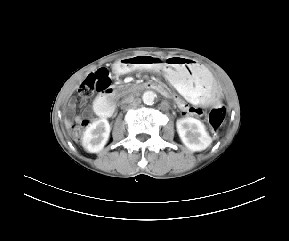

病变位于肝胃间隙,实际就是位于小网膜囊(左肝下后间隙),呈轻度不均匀性强化,腹腔内及腹膜后见多发肿大淋巴结。所以我考虑肝胃间隙恶性胃肠间质瘤并淋巴结转移。

病灶强化不显著,灶周及腹膜后见多量淋巴结肿大,考虑淋巴瘤可能,其次考虑间质瘤

肝胃韧带内及腹膜后可见多发增大的淋巴结影,首先考虑转移.